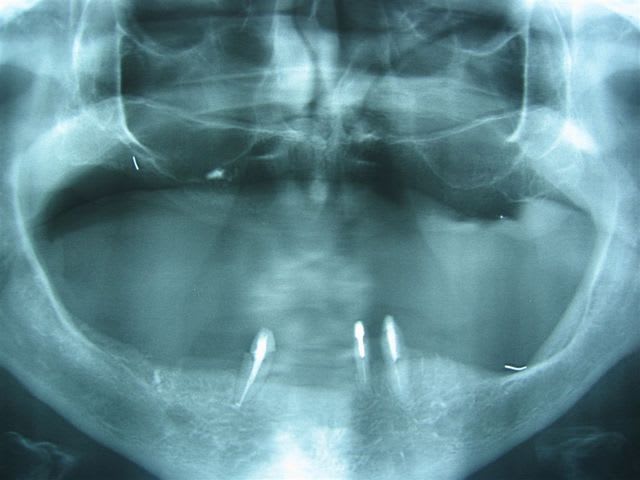

21/08/2006 à 13h09

... ganglion calcifié

L - Eugenol